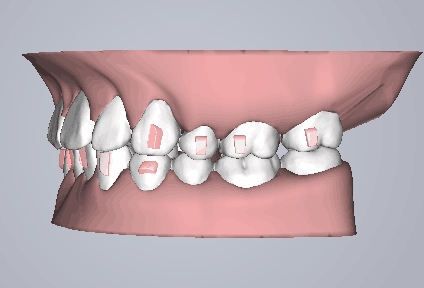

该技术可根据求美者的颌面形态开展个性化设计,通过计算机三维图像技术模拟牙齿移动后生产的每一副矫治器,在戴入后牙齿就会有受力感觉,并向矫治器设计的位置移动,通常每两周更换一副矫治器,牙齿就会从初始的畸形状态逐渐移动至正常排列状态,矫治时间长短取决于患者牙颌畸形的严重程度,一般需要半年到一年时间就能解决牙齿不齐等问题,该技术成为国内外爱美人士矫正牙齿的不二选择。

2应用时代天使无托槽隐形矫治器进行矫治。

3排齐排平,内收上下前牙,改善上下颌前倾和前突面型,协调上下颌咬合,保持!

治疗方案动画

治疗预计效果和实际效果